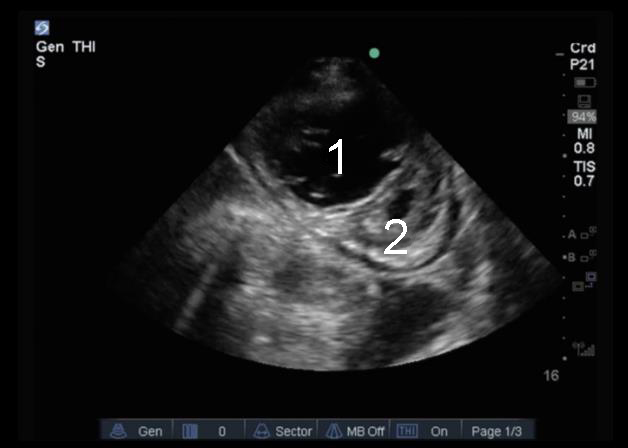

Heart Parasternal Short Axis (PSAX) Potential Cor Pulmonale Image

1. Right Ventricle (RV)

2. Left Ventricle (LV)